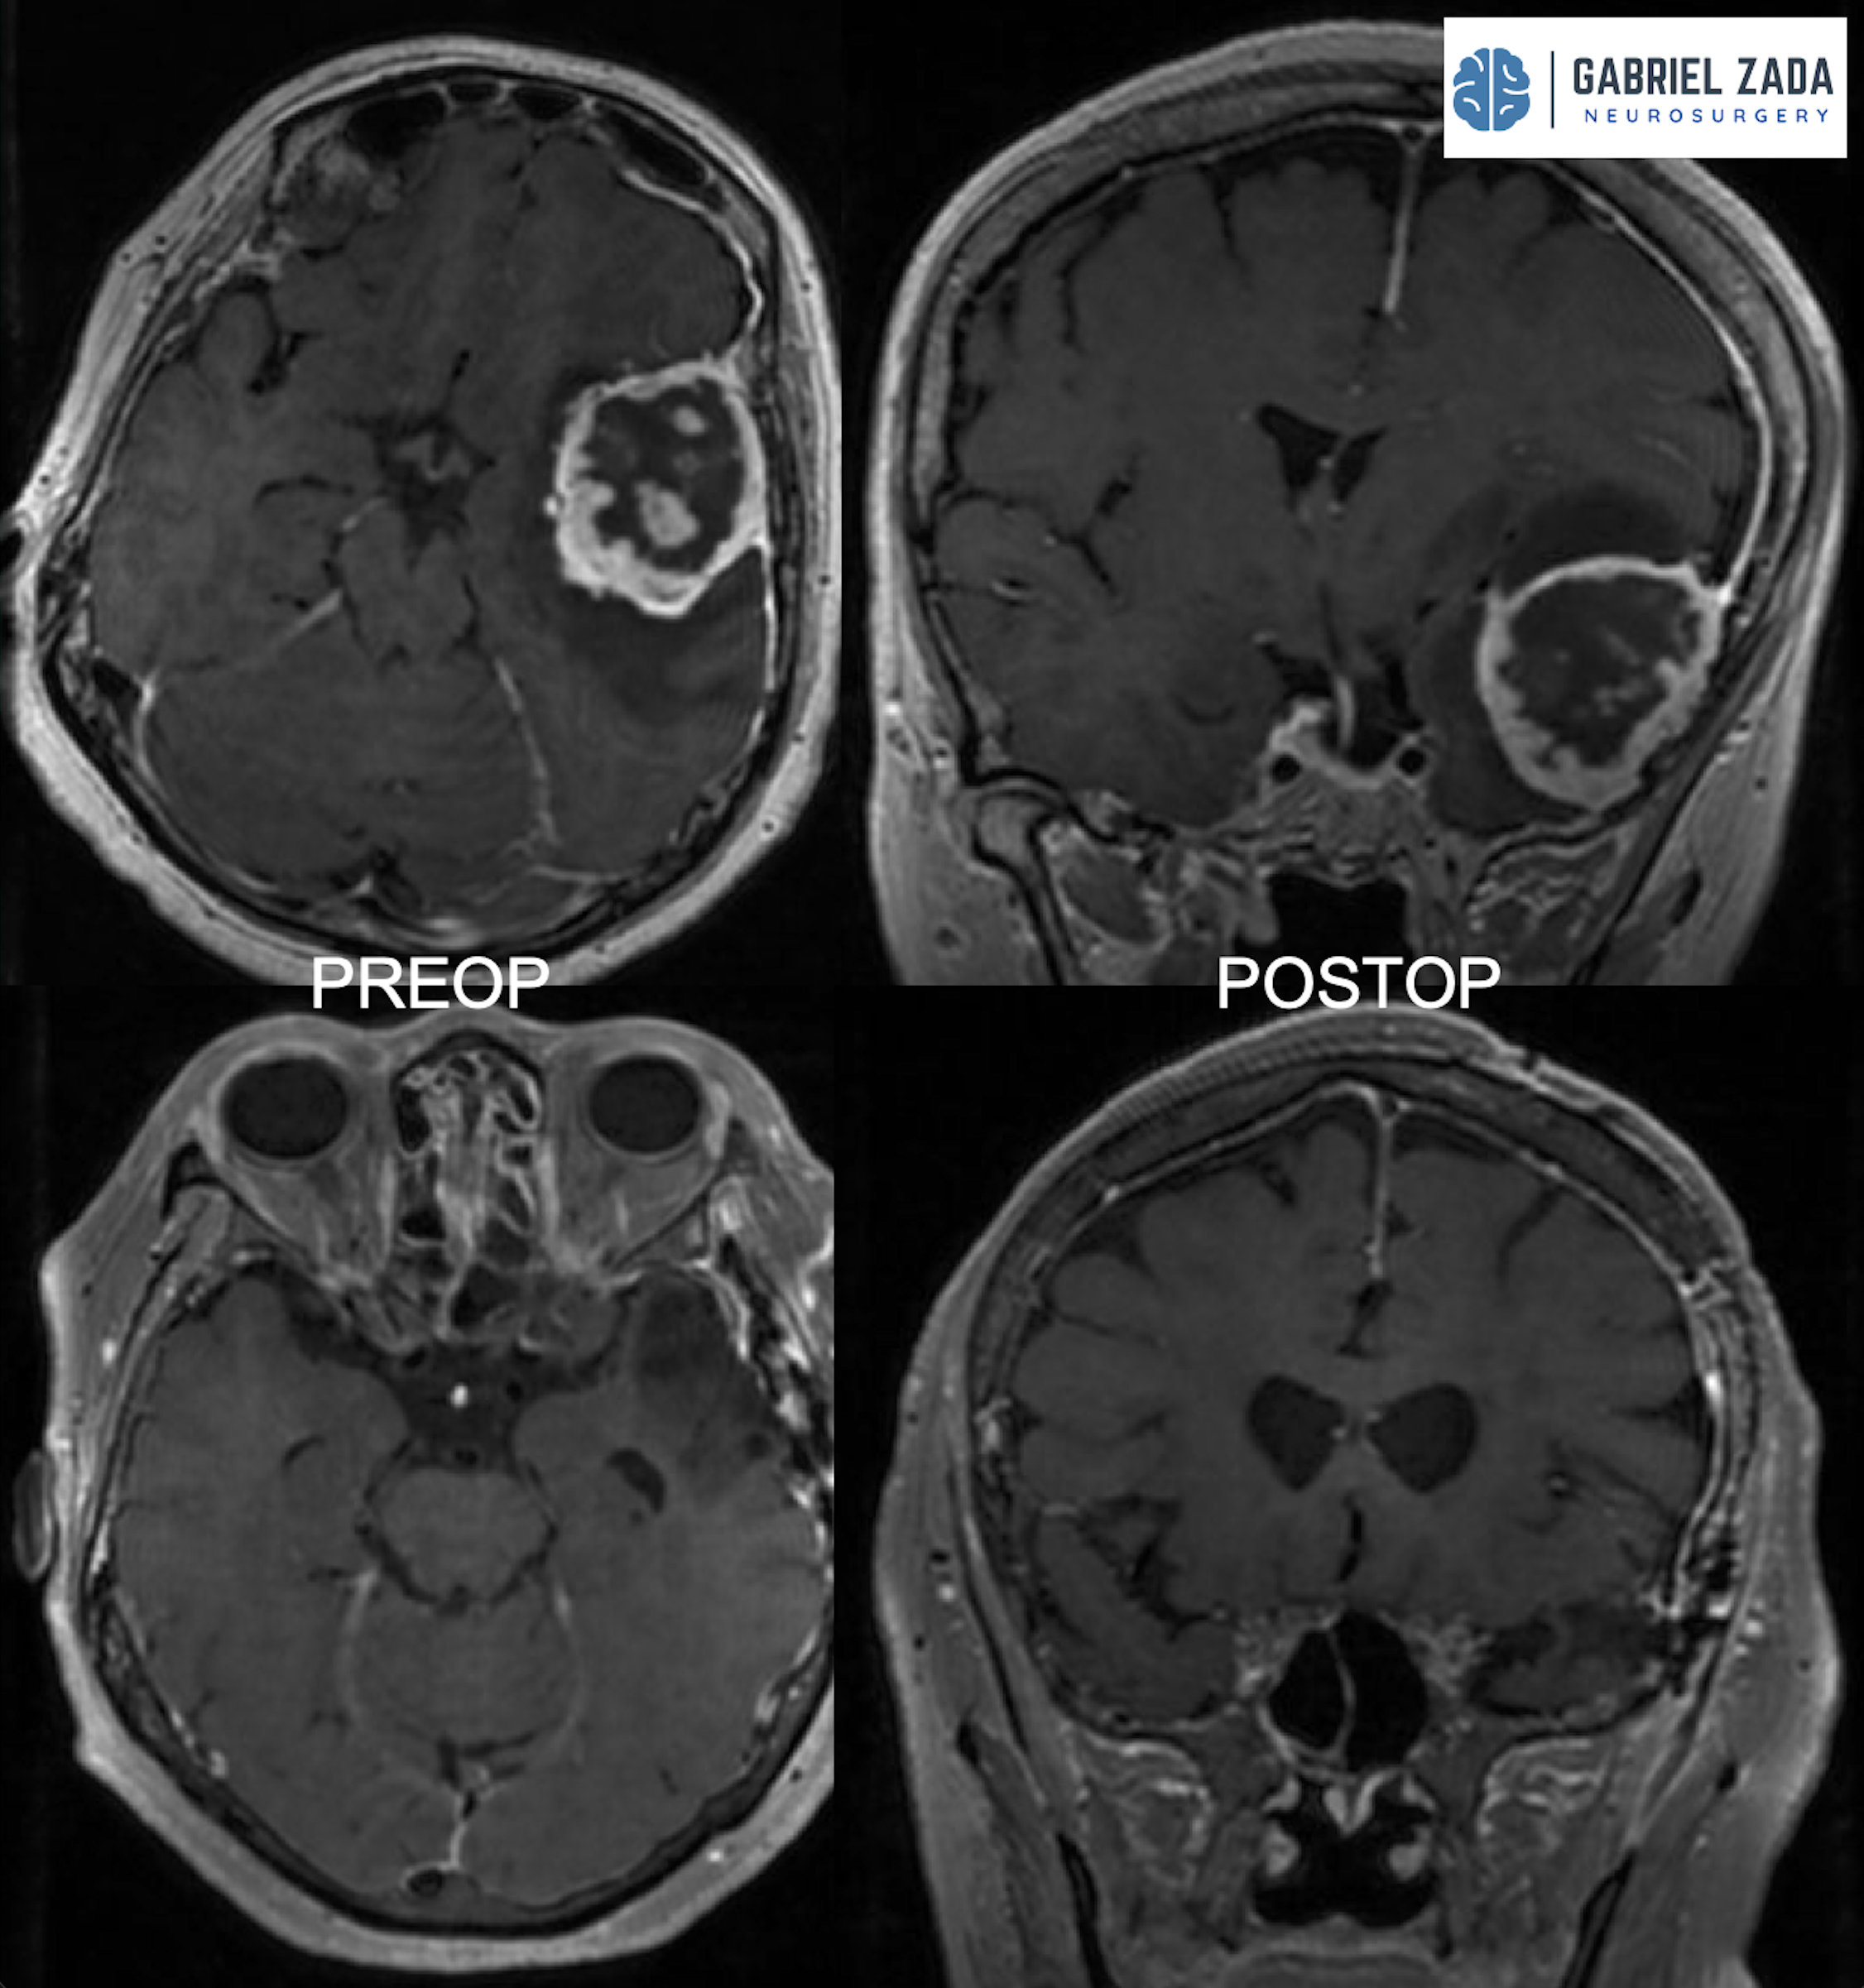

Explore this comprehensive gallery featuring pre‑ and post‑operative imaging of patients with skull‑base tumors treated by Gabriel Zada, MD, MS, FAANS, FACS. These cases highlight Dr. Zada’s expertise in advanced neurosurgical techniques and outcomes.

*Representative cases shown for educational purposes. All images de-identified. Individual results vary.